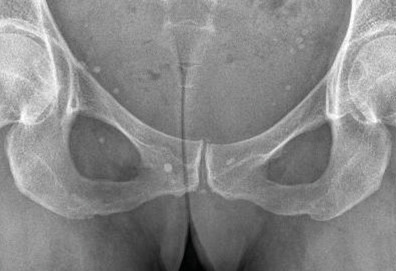

L’arthrose associée aux dépôts de PPC touche en particulier les genoux, avec une symptomatologie chronique et/ou des accès aigus cristallins. Par comparaison avec l’arthrose idiopathique, elle serait à l’origine d’une symptomatologie plus inflammatoire, toucherait des articulations inhabituelles (radiocarpienne, carpienne, gléno-humérale, médio-pied et arrière-pied, cheville) et serait associée à plus d’ostéophytes et de géodes. Cette arthropathie dégénérative peut s’accompagner de lésions structurales sévères avec disparition rapide de l’interligne (arthropathies destructrices : hanches, genoux, poignets, coudes). Les objectifs et les modalités thérapeutiques sont identiques à ceux d’une arthrose idiopathique. Aucun traitement ne permet la dissolution des cristaux de PPC.

La forme pseudorhumatoïde est rare (5 %), simulant une polyarthrite rhumatoïde (diagnostic différentiel), avec parfois des signes systémiques d’inflammation (élévation de la vitesse de sédimentation et de la CRP). Le diagnostic repose sur la mise en évidence des cristaux de PPC. La radio peut mettre en évidence des calcifications des cartilages articulaires (fig. 6) et des fibrocartilages (fig. 7, 8, 9 et 10). L’échographie (plus sensible) peut mettre en évidence des dépôts de PPC, qui apparaissent comme une fine bande hyperéchogène au sein des cartilages hyalins et comme des points scintillants dans les fibrocartilages ou dans la membrane synoviale. Dans l’arthrite chronique à PPC, lespossibilités thérapeutiques sont, par ordre de préférence : colchicine (de 0,5 à 1 mg/j), petites doses de cortisone, parfois les AINS per os (mais leur prescription est souvent limitée par les comorbidités chez les patients âgés), méthotrexate et l’hydroxychloroquine. Il n’y a pas aujourd’hui de traitement « de fond », mais des molécules sont à l’étude.